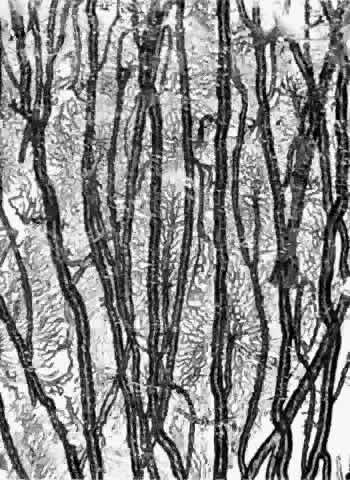

Torczynski and Tso27 reported on the architecture of the choriocapillaris in the posterior pole after examining choroidal flat preparations and transverse and oblique histologic sections (Figs. 21, 22, and 23). They described the overall appearance of the posterior choriocapillaris as a series of adjoining lobules that was striking in some preparations and subtle in others. The center of the lobule consisted of a single precapillary arteriole rimmed in a thick mantle of collagen measuring 15 to 25 μm and opening perpendicularly or curvilinearly into a capillary bed that radiated an average distance of 300 to 400 μm before changing from a radial to a circumferential direction. The circumferential capillaries in the periphery of the lobule were wider and converged from several directions, forming star-like or dendritiform configurations in the plane of the choriocapillaris. Venular openings, outward bulgings of the external choriocapillaris called atria, measured 30 to 37.5 μm and were present singly and in linear sequences underlying the circumferential capillaries. The often incomplete lobules varied in their geometric configuration, having three to six sides and ranging in area from 420 × 605 μm to 800 × 1200 μm. The lobular unit was thought to provide a preferred outflow route via the perimeter of postcapillary venules so that cross-flow from lobule to lobule would not normally occur, and thus the precapillary arteriole would function as an end-arteriole.

Fig. 21. Flat preparation of choriocapillaris, posterior pole. A. Arrowheads indicate oval openings to the postcapillary venules. The area around the precapillary arteriole (white-bordered arrow) is stained more heavily because of residual subcapillary collagen. (PAS, × 180; AFIP Neg 74-9984) B. Postcapillary venules (arrowheads) form an irregular ring bordering the capillaries that radiate from the precapillary arteriole (white-bordered arrows), thus outlining a single lobule. The capillaries are broader and clearer near the venules because of less subcapillary collagen. (PAS, × 100, AFIP Neg 74-10240) C. The openings of the postcapillary venules (as shown above) are connected with black lines; they demarcate adjoining lobules in the choriocapillaris. Capillaries from adjoining lobules enter the intervening venules. The lobules form a mosaic of adjoining vascular beds. Precapillary arterioles are indicated by white-bordered arrows. (PAS × 55; AFIP Neg 74-9985)

Fig. 22. Choriocapillaris in periphery has long, thin intercapillary septa. Arteriole in capillary plane (curved arrow). Venous anastomosis (arrowheads). (AFIP Neg 73-11415 and 12110; PAS, × 50)

Fig. 23. Prominent lobular pattern in choriocapillaris with venules (arrowheads) surrounding arterioles (arrows). (AFIP Neg 75-3895; PAS, × 55) (Torczynski E, Tso M: The architecture of the choriocapillaris at the posterior pole. Am J Ophthalmol 81:428, 1976)